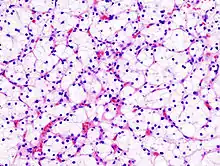

Generally, the cells have a clear cytoplasm, are surrounded by a distinct cell membrane and contain round and uniform nuclei.

Clear-cell renal-cell carcinoma. HE, × 100

Clear-cell renal-cell carcinoma. Fuhrman grade = 1. HE, × 400